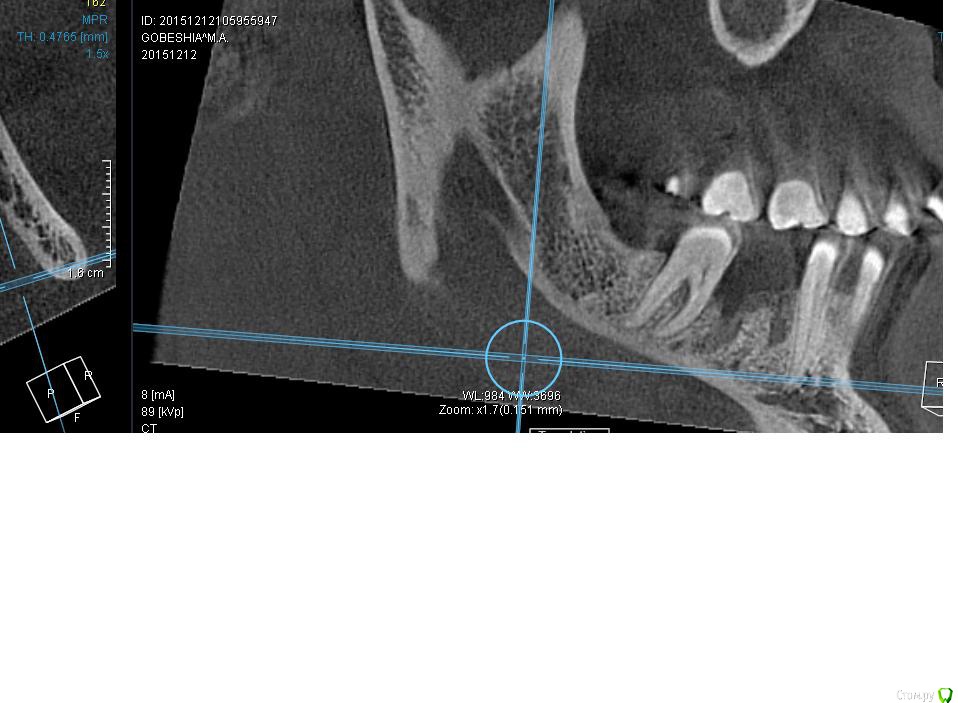

Макс111 Опубликовано 16 декабря, 2015 Автор Поделиться Опубликовано 16 декабря, 2015 https://yadi.sk/i/NCV5zBsrmFzW3вот так получилось сделать с этого кт, а нижний как сделать не знаю Ссылка на комментарий

Макс111 Опубликовано 16 декабря, 2015 Автор Поделиться Опубликовано 16 декабря, 2015 вот так еще получилось сделать Ссылка на комментарий